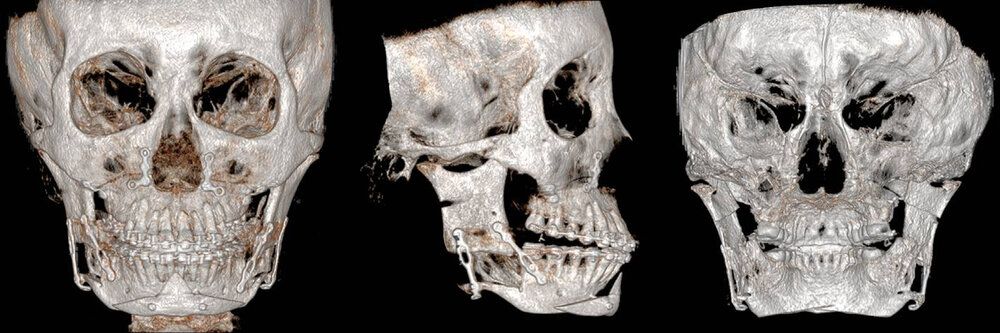

Fig.2. Visualization of the osteotomy line in a three-dimensional reconstruction of postoperative CBCT, front view (left), right profile (middle) and rear view (right).